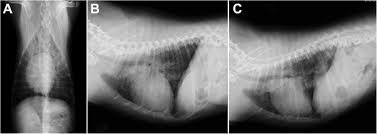

Lateral thoracic radiograph from a dog with a ventral alveolar pattern.

Lateral thoracic radiograph from a dog with a ventral alveolar pattern. That still leaves the question of why you should have recurrent pneumonia, unanswered and that is a question that will require further investigation. You can see on the left of the image a dark (relatively clear) lung. Pneumonia in people with lung cancer. The cause can be bacteria, a virus, or fungi. The problem here is that many things can enlarge the spleen above and beyond cancer. Note the increased soft tissue opacity in the lungs that partially obscures blood vessel margins. Various viruses, bacteria, and fungi can cause pneumonia. Differential diagnosis for common lung patterns in dogs and cats. I am a severe asthmatic and have had pneumonia on several occasions. This can happen when there is a high suspicion of cancer, for example, an enlarged spleen in a dog who is not acting right. Your veterinarian may recommend an fna and cytology or a biopsy, to confirm the diagnosis, and determine exactly what kind of lung cancer is present. Primary lung cancer are frequently located in the caudal (towards the hind end of the pet) lung lobes, however can be located in any lung lobe and are usually a single mass in the lungs, unless the tumor has spread.

Bacterial culture and drug sensitivity testing help the veterinarian to determine the best course of antibiotic treatment, if needed. His appetite is basically normal though his blood work shows that he is anemic. They did a cat scan and said the nod was.08 or 08 centimeters in dia. Note the increased soft tissue opacity in the lungs that partially obscures blood vessel margins. Bacterial pneumonia is an inflammation of the lung usually caused by bacterial or viral infection but can be caused by inhalation of an irritant. I am a severe asthmatic and have had pneumonia on several occasions. Your veterinarian may recommend an fna and cytology or a biopsy, to confirm the diagnosis, and determine exactly what kind of lung cancer is present. That still leaves the question of why you should have recurrent pneumonia, unanswered and that is a question that will require further investigation. The end stage of lung cancer in dogs is a very difficult time for dog owners as it's very hard to watch a beloved companion start giving up on life. Note the lobar sign with the caudal lung lobe. As these can also be caused by other disease, diagnostics include a full physical exam, blood work, radiographs, and may also require bronchoscopy with. A definitive diagnosis of lung cancer requires a sample of tissue (biopsy). This can happen when there is a high suspicion of cancer, for example, an enlarged spleen in a dog who is not acting right.